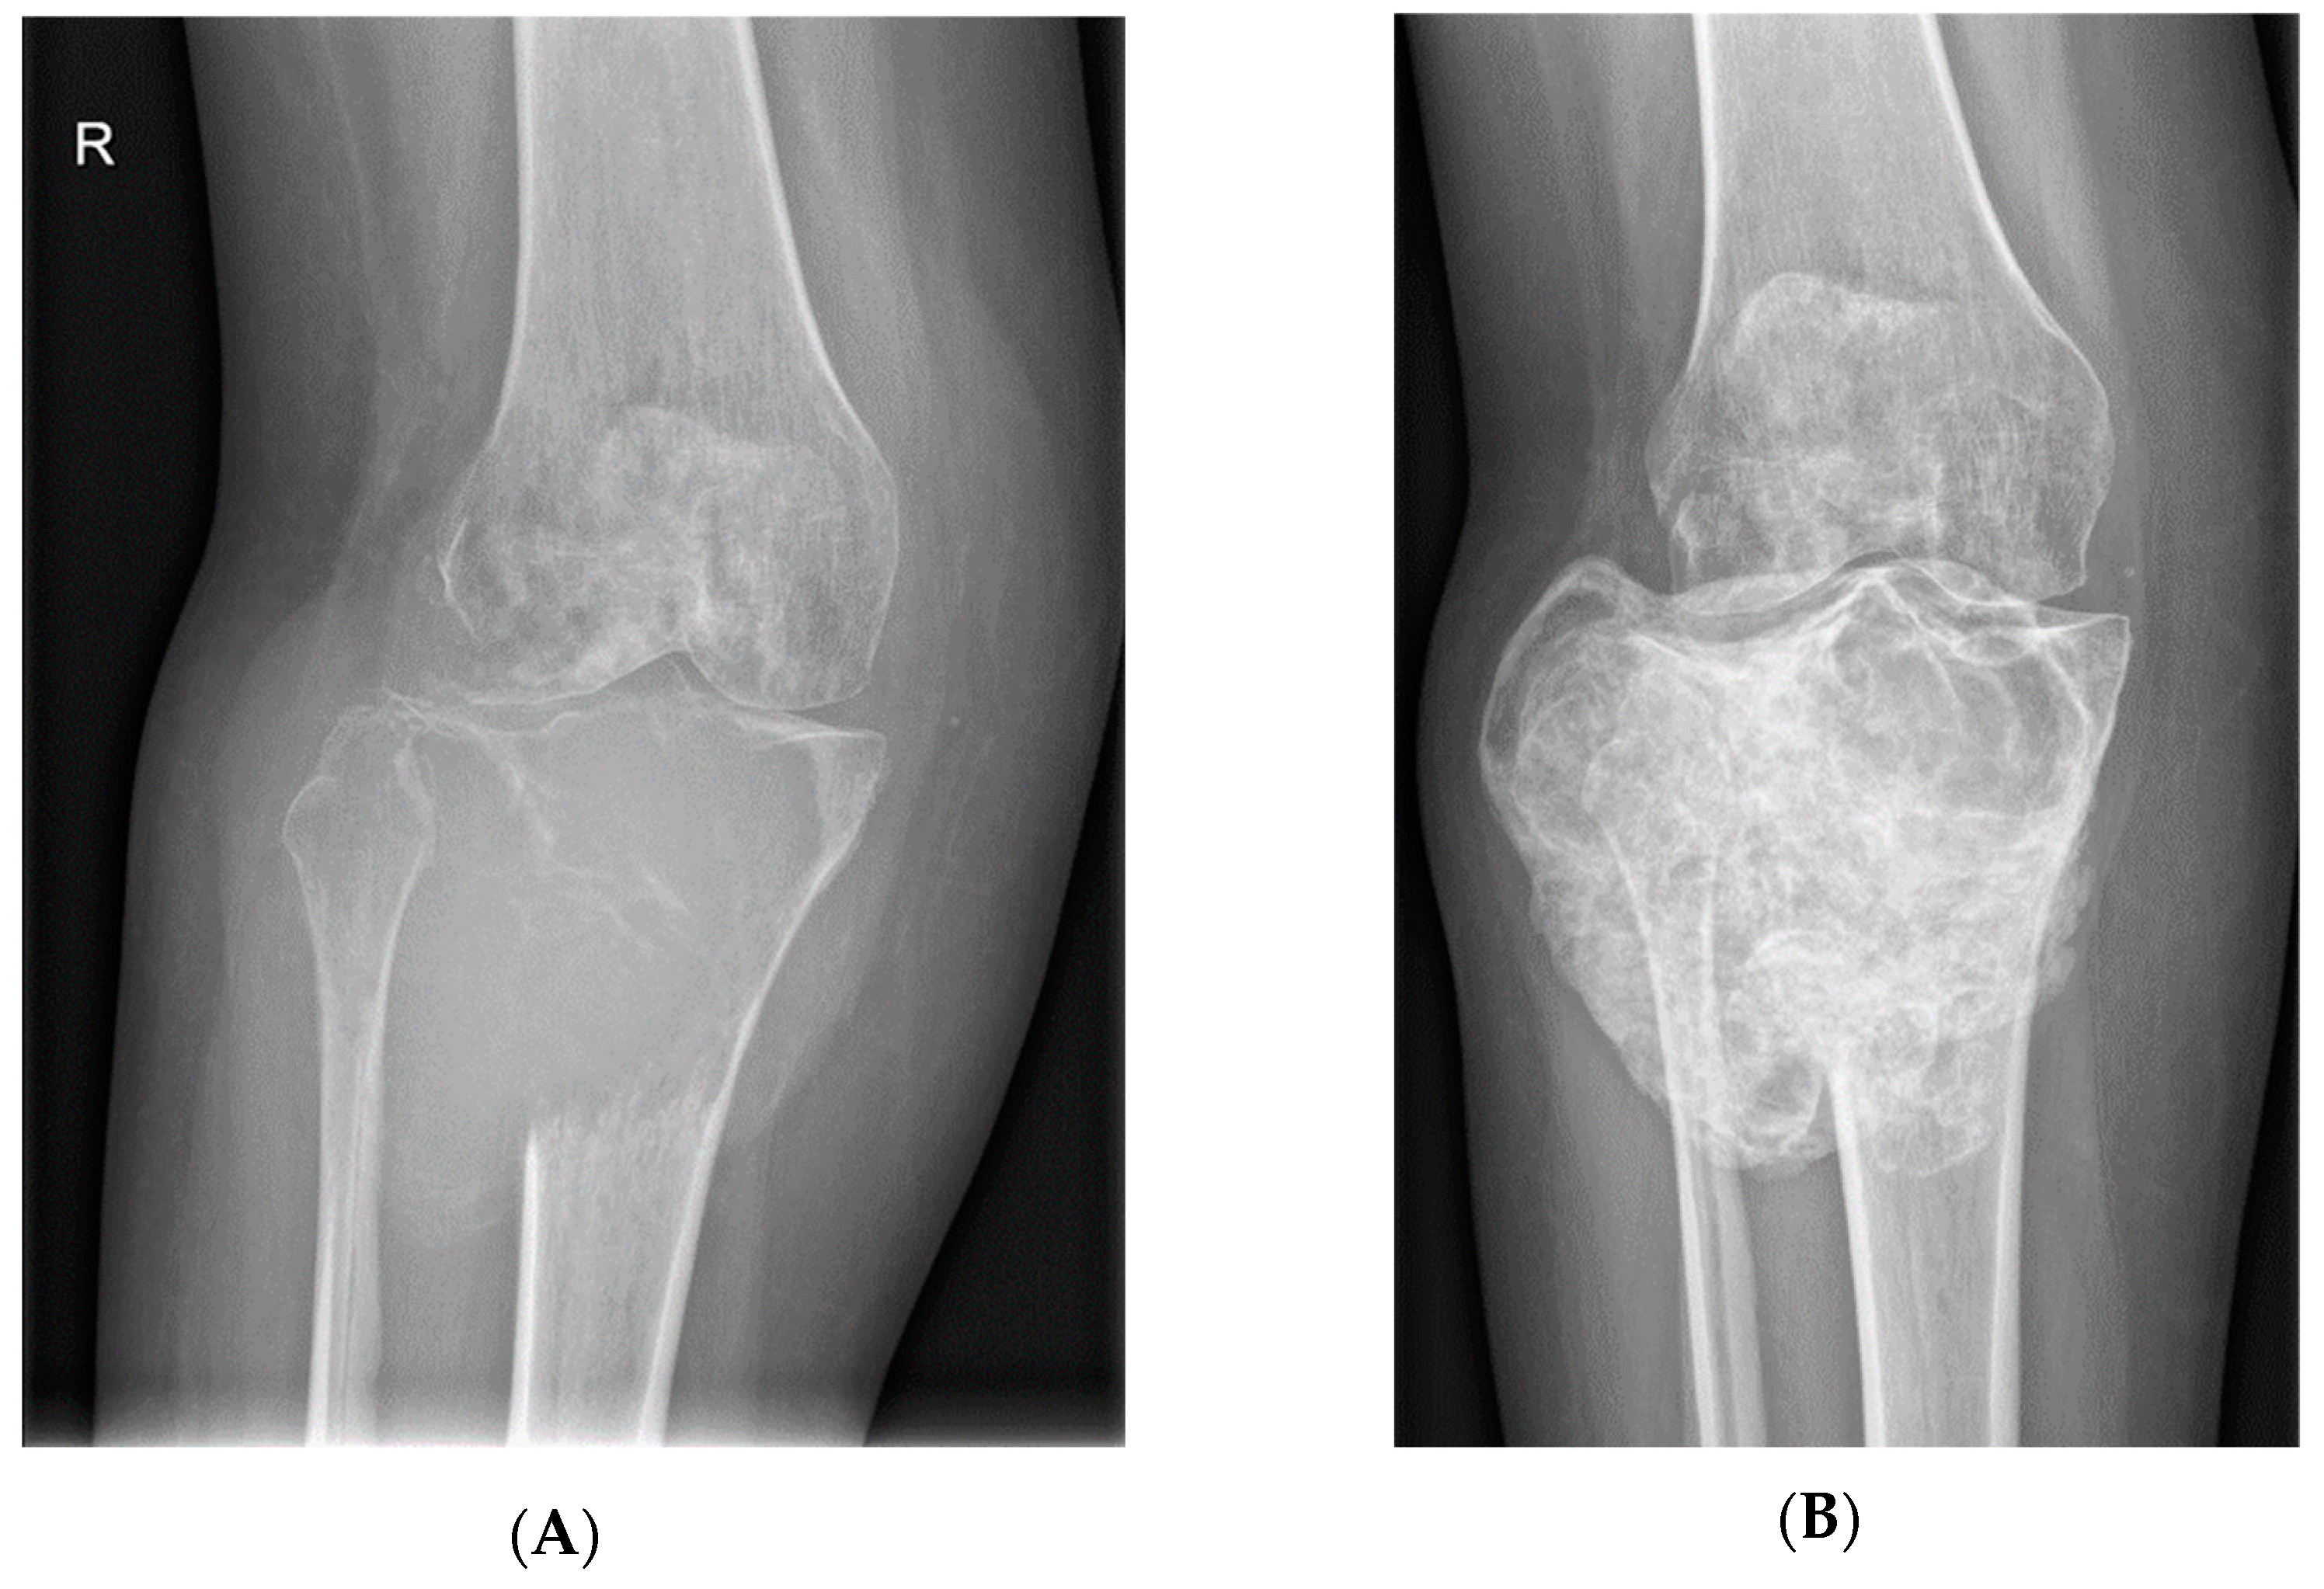

- Van Langevelde, K.; McCarthy, C.L. Radiological findings of denosumab treatment for giant cell tumours of bone. Skelet. Radiol. 2020, 49, 1345–1358. [Google Scholar] [CrossRef] [PubMed]

- Murphey, M.D.; Nomikos, G.C.; Flemming, D.J.; Gannon, F.H.; Temple, H.T.; Kransdorf, M.J. Imaging of Giant Cell Tumor and Giant Cell Reparative Granuloma of Bone: Radiologic-Pathologic Correlation. RadioGraphics 2001, 21, 1283–1309. [Google Scholar] [CrossRef]

- Oguro, S.; Okuda, S.; Sugiura, H.; Matsumoto, S.; Sasaki, A.; Susa, M.; Morioka, H.; Jinzaki, M. Giant Cell Tumors of the Bone: Changes in Image Features after Denosumab Administration. Magn. Reson. Med. Sci. 2018, 17, 325–330. [Google Scholar] [CrossRef]

- Hakozaki, M.; Tajino, T.; Yamada, H.; Hasegawa, O.; Tasaki, K.; Watanabe, K.; Konno, S. Radiological and pathological characteristics of giant cell tumor of bone treated with denosumab. Diagn. Pathol. 2014, 9, 111. [Google Scholar] [CrossRef]